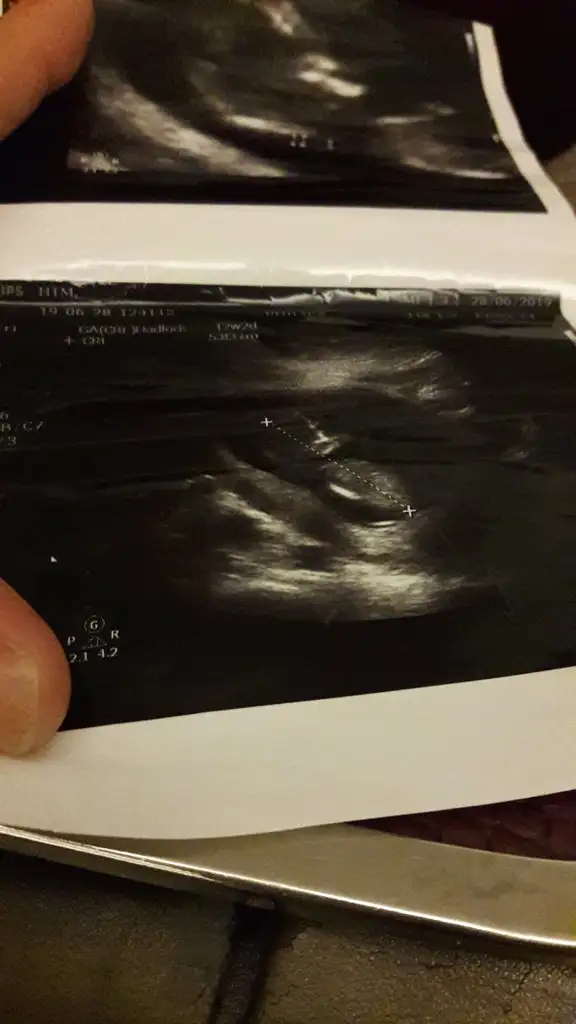

Canım bariz belli bence erkek 😊Rabbim gonlundekini hayırlı eylesin

Amin canım cümlemizin inşallah ☺️ Doktor erkek dedi ama bi ihtmal kesin konuşmadı zaten ama 2 li için radyolojiden girdim ultrasona orda başka dr görsem söylerim ama erkek diyemem dedi kafam karıştı

merhaba 12+0 acaba yorumlayabilir misiniz ben cıkintı gormedim